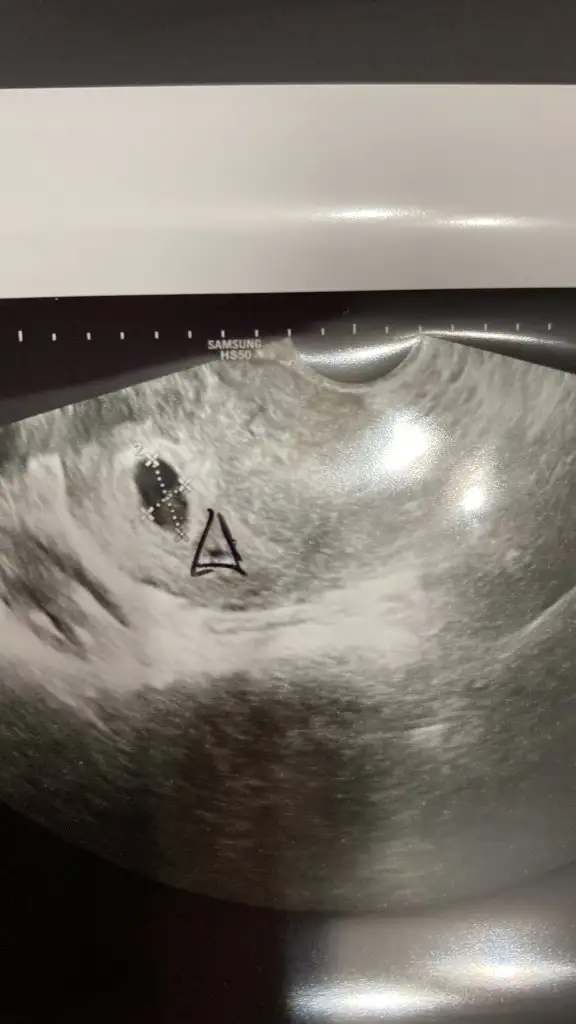

Benimde 5+3 de kese 6+3 de bebek görülmüştü yanı gözükmemesi çok normalgunaydin anneler ve Anne adaylari

Dun ilk kontorole gittim 5 hafta ve 1 gun

keseyi gordum fakat embriyo yoktu ve kesenin yaninda bir nokta gibi yuvarlak bisey Daha vardi doktorum intravajinal takmam gereken bir ilac Verdi o yuvarlagin kapanip hamileligi desteklemesi icin . Gogus hassasiyetim veya baska bir berlirtim yok sadece basim cok kotu agriyor kac gundur . Doktor 2 hafta o ilaci kullaip 10 gun Sonra tekrar gelip bebegin gelip gelismedigini gormek icin cagirdi . Icimde kotu bir His var . Oglumda 4 haftalikkrn kesede gorulmustu . Bos hamilelik olucak diye cok korkuyorum .

Sizde bebekleriniz kesede kacinci haftada goruldu ?